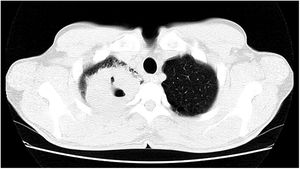

Paciente do sexo masculino, 47 anos de idade, tabagista, relatou aparecimento de petéquias, púrpuras palpáveis e bolhas hemorrágicas nas plantas e palmas (fig. 1) havia uma semana, progredindo para membros inferiores, superiores, abdome e face (fig. 2), além de sangramento ocular, nasal, hemoptise e febre. A tomografia do tórax revelou cavitações com paredes espessas no lobo superior direito com consolidações esparsas em outras áreas pulmonares (fig. 3).